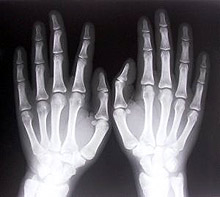

В областта на диагностиката и лечението важен е изборът на 56 центъра по остеопороза, подчерта министър Гайдарски. Предвидено е разработване на методически указания за инструментална диагностика на остеопорозата, както и организиране на квалификационни курсове за специалистите, осъществяващи инструментални и лабораторни изследвания в тази област.

В началото на 2007 година ще бъде готов и фармакоикономическият анализ на лечението на остеопорозата, който е в основата на евентуални предложения за реимбурсация на медикаментите за хора с диагностицирана остеопороза, каза Гайдарски и допълни, че се изготвят оценка и анализ на разходите на здравеопазването за лечение и рехабилитация на болните от остеопороза и на социалните разходи, възникващи при случаите с остеопорозни фрактури.